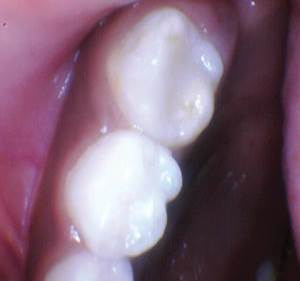

Caso 3

La caries recurrente en un diente primario que involucra múltiples superficies generalmente conduce a una cobertura total y con razón. Sabemos que los materiales a base de resina tienen fugas en ambientes hostiles ácidos y acribillados de sacarosa; por lo tanto, se recomienda una cobertura total en estos casos. ¿Qué pasaría si pudiéramos restaurar con un material más estético para los padres estéticos? En estos casos estéticos, todavía necesitamos resistencia y un material activo no inerte.

Figura 1. Fotografía preoperatoria del segundo molar primario superior derecho con caries distoocluso-bucal. En el pasado, al menos para mí, el tratamiento habría sido una corona de cobertura total (probablemente de acero inoxidable). Debido a las preocupaciones estéticas de los padres, es bueno tener una opción alternativa, especialmente un material que sea activo dentro del entorno oral. |

Figura 2. La caries se excavó y se eliminó todo el esmalte socavado. |

Figura 3. Se colocaron una banda y una cuña. Activa Bioactive Restorative A2 fue colocado, curado, acabado y pulido. |